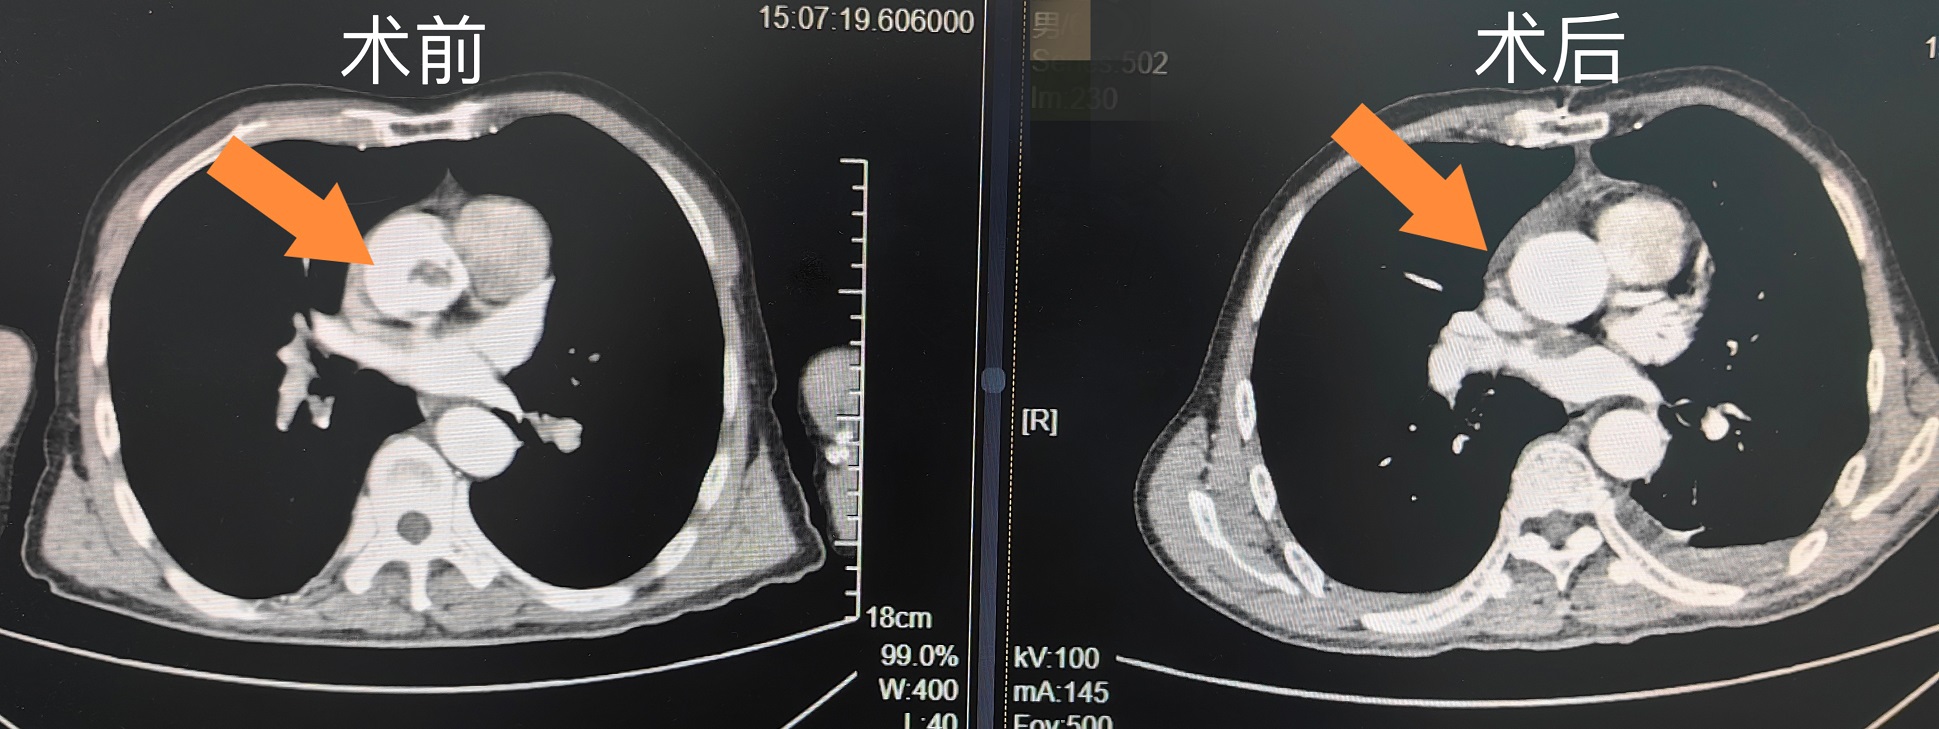

该患者的血栓位于升主动脉近窦管交界部,范围约:23mm×14mm×22mm,众所周知,升主动脉内高速血流和高压环境,血栓形成极其少见,而此部位血栓脱落可导致急性心肌梗死、卒中或周围动脉栓塞,随时危及患者的生命安全。

该患者因上腹部疼痛,腹胀伴肛门停止排气排便5天,伴呕吐。由当地医院紧急转入中南大学湘雅三医院胃肠外科,诊断为完全性肠梗阻,积极完善相关术前检查,4月1号为患者实施剖腹探查术+右半结肠切除+回肠造瘘术,6号夜间患者出现腰背部的剧烈疼痛,8号行CT检查提示右肾部分梗死和主动脉根部血栓形成。结合患者病史,血栓部分脱落也是导致患者肠梗阻及右肾部分梗死的“真凶”,胃肠外科10号组织心胸外科、泌尿外科、感染科、呼吸科、临床药学等相关科室进行了疑难病例讨论及多学科MDT会诊。

患者血栓存在的位置,就像一颗“炸弹”,随时会因血液快速流动,高压血流冲击导致栓子脱落,危及生命,需要尽快转心胸外科以手术的方式将栓子取出来,同时迅速完善相关检查为手术做准备。手术前,王电军教授带领其团队成员针对病例的特殊性和危险性进行了充分的术前讨论,制定了具体的手术实施方案。经过周密的准备,12号在麻醉科和手术室的保驾护航下,由王电军教授主刀,在邓柳平医师等人的共同协作下成功为患者实施了主动脉内血栓清除术,手术后在心胸外科医疗护理团队的精心照顾下顺利度过危险期,术后第3天转回普通病房,术后第5天患者已能下床活动,21日已顺利出院。